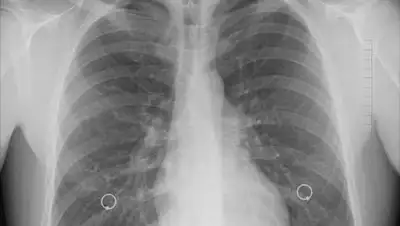

По словам хирурга, легкие курильщика довольно пятнистые и "туманные". Пациент с Covid имеет полностью "белые" легкие. Это связано с интенсивным рубцеванием, вызванным коронавирусом и недостатком воздуха.

Я не знаю, кому нужно это знать, но пост-ковидные легкие выглядят хуже, чем легкие любого курильщика, которые мы когда-либо видели. Они рушатся и тромбуются. Одышка продолжается и продолжается, - написала она в Twitter.

Хирург опубликовала три рентгеновских снимка:

Легкие выздоровевшего ковид-пациента

Легкие курильщика

Легкие здорового человека